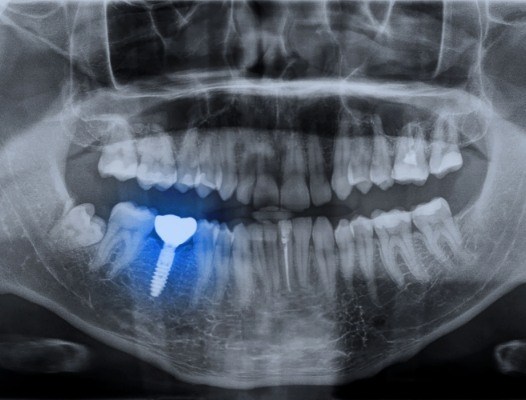

Natural teeth are made up of two parts: the shiny white crown that you see when you smile, and the hidden roots under the gums that hold it in place. Other tooth replacement options like dentures and dental bridges only replace the crowns of missing teeth, which only fixes some of the issues associated with tooth loss. On the other hand, dental implants are designed to replace the entire structure of a missing tooth from top to bottom for the best, most lifelike results.

A dental implant is a small titanium post that can be inserted into the jawbone. This allows it to mimic the roots of a missing tooth and provide a strong foundation for the replacement teeth. A connector piece called an abutment sits on top of the post and secures a restoration in place. This could be a custom-made crown, bridge, or denture depending on how many teeth you are missing. Thanks to this unique placement, the end result is a smile that looks, feels, and functions just like natural!